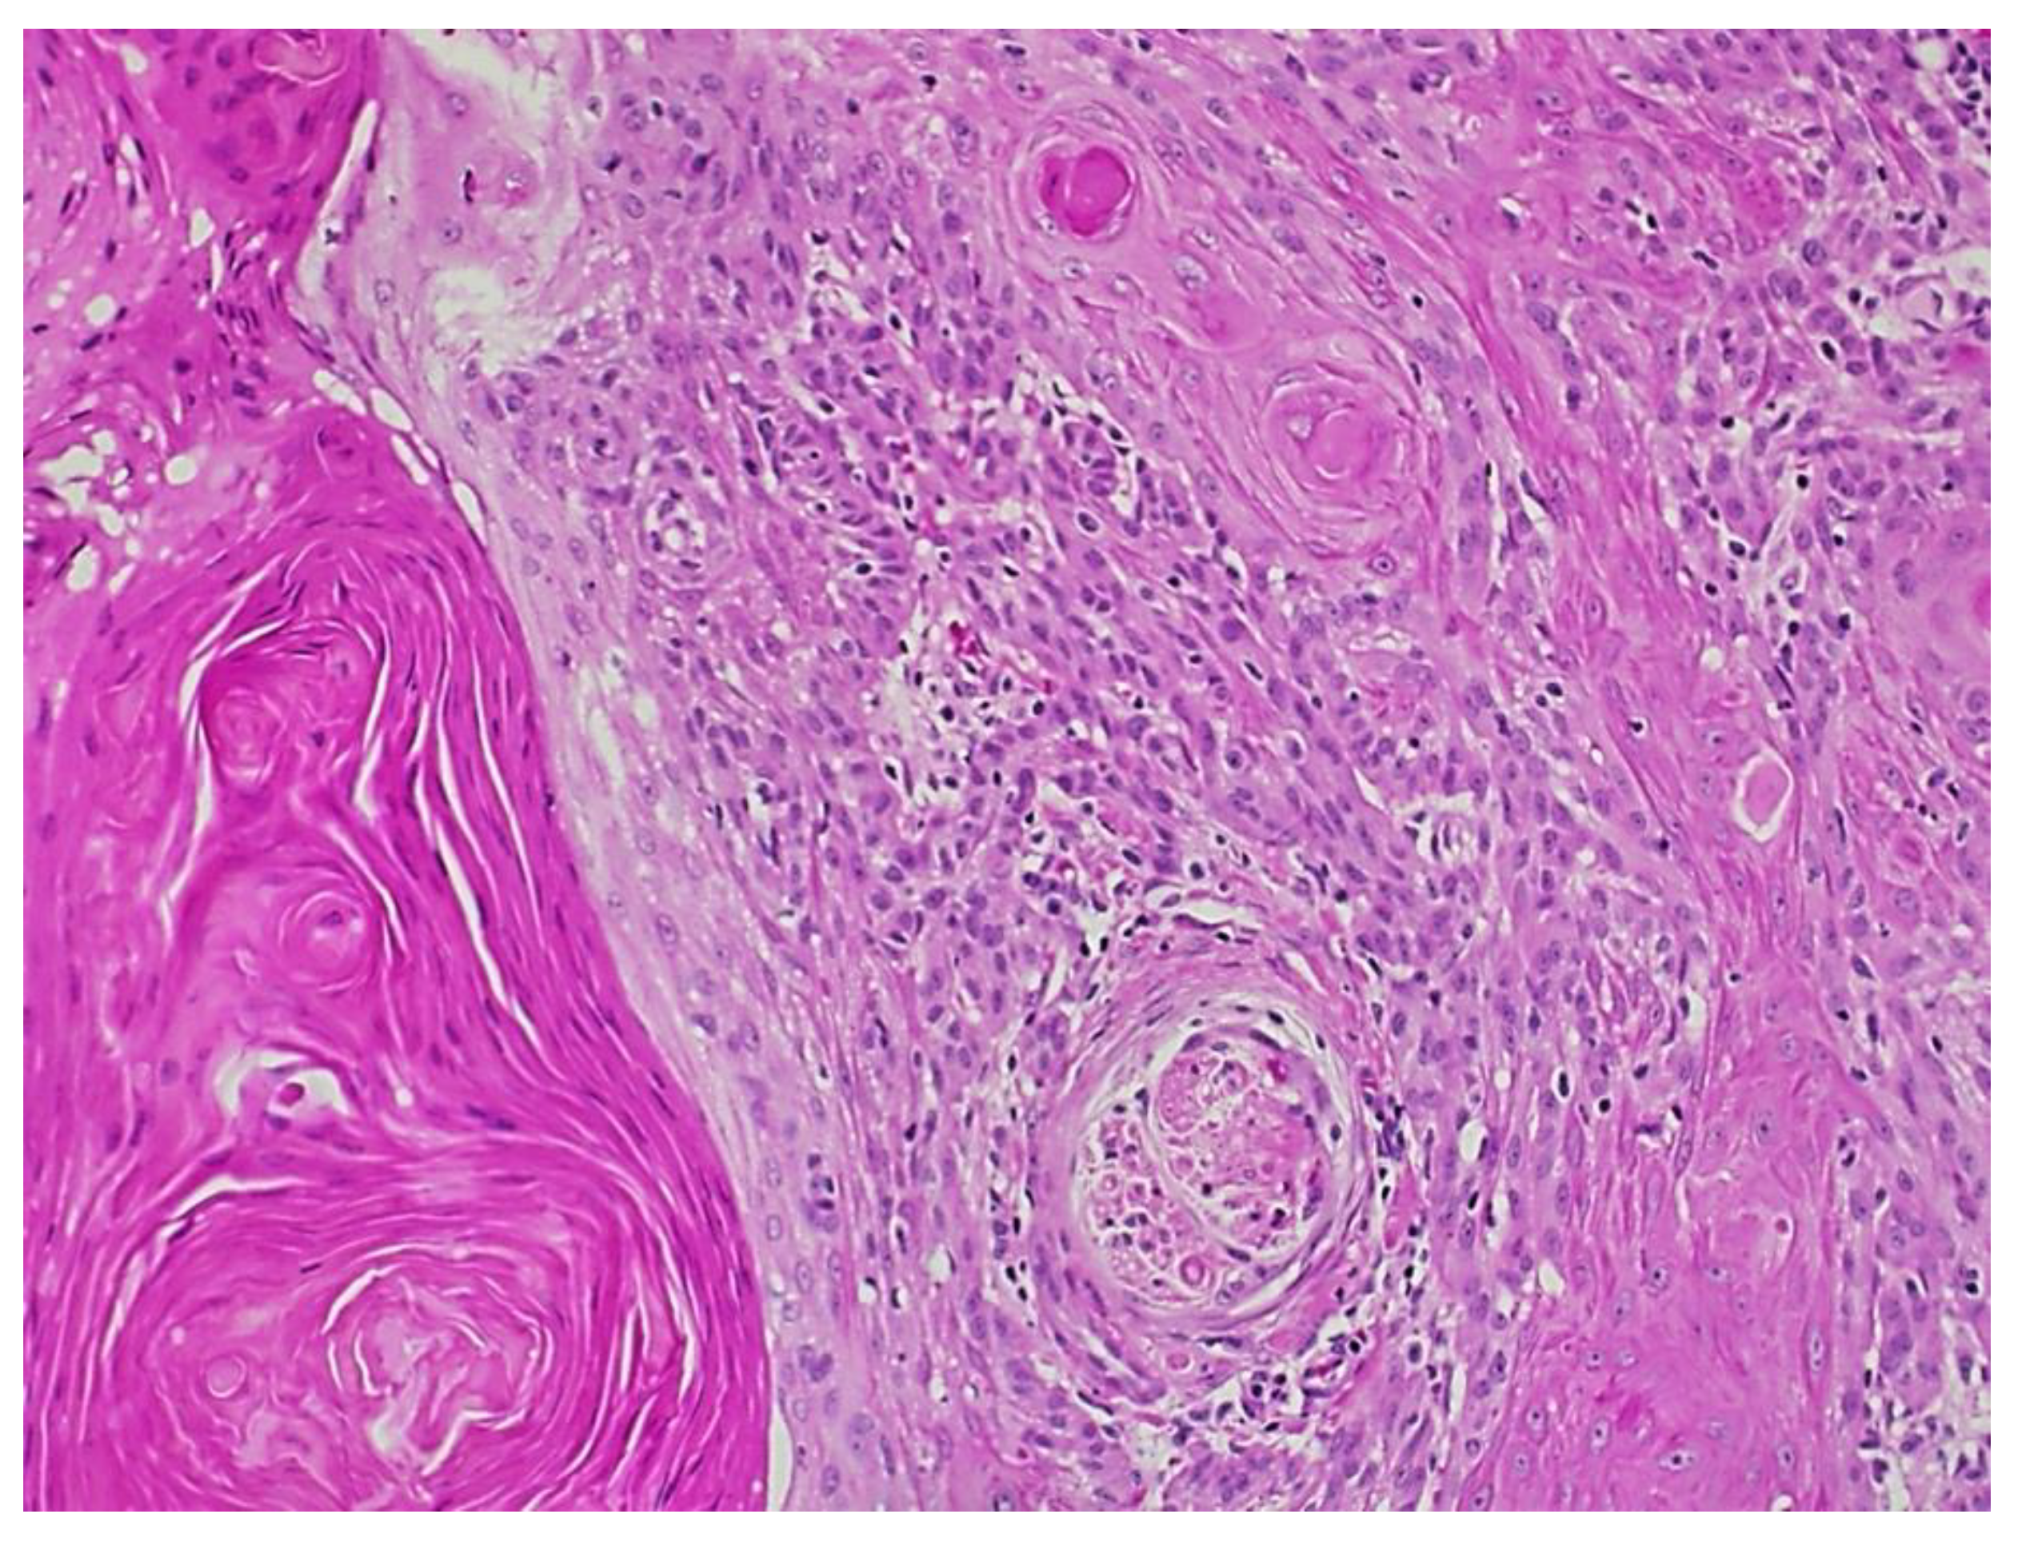

Figure 3.

Squamous cell carcinoma with acantholytic features.

Fourteen years after the transplant, the patient was seen in dermatology for a morbilliform drug eruption to clindamycin, which was treated with six weeks of oral prednisone. While being followed for her drug eruption, she developed a rapidly growing 3.5 cm fungating, ulcerated, and slightly tender nodule on her right dorsal hand. (Figure 2) Punch biopsy revealed a cutaneous squamous cell carcinoma with acantholytic features. (Figure 3) Immunohistochemical staining for P16 was negative. This test was performed to rule out co-infection with HPV.